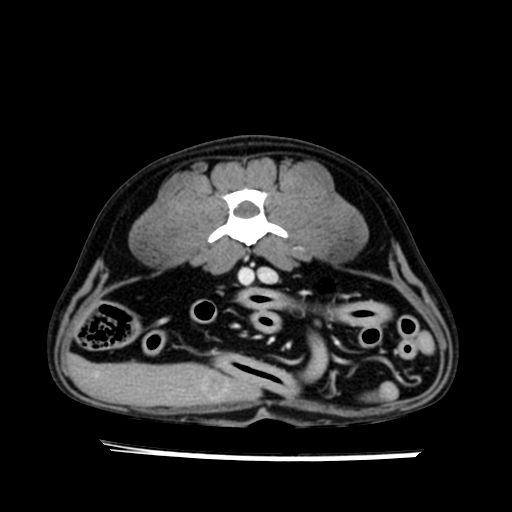

prescritto esame TAC

sequenza immagini limitata al fegato reni e surreni

le immagini ecografiche rispetto alla tac datano circa 7 mesi prima ,le surrenali sono normali nonostante il test acth sia risultato positivo .all’esame TAC dopo diversi mesi risultano aumentate armonicamente nel volume e si individua un forte sospetto di adenoma ipofisario .

sospetto adenoma ipofisario vs. meno probabilmente meningioma della base; intertiziopatia polmonare; lesione espansiva epatica, verosimilmente del lobo laterale sinistro, di sospetta natura neoplastica; lesioni spleniche di natura da definire; iperplasia/ipertrofia delle ghiandole surrenali, bilateralmente; vertebra di transizione del rachide toracico; tenosinovite cronica del muscolo bicipite brachiale di destra.